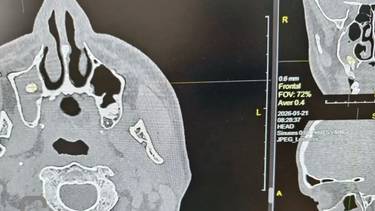

Фото: ГАУЗ ГБ Орска

Доктора Орской городской больницы провели уникальную операцию, вернув пациенту способность полноценно дышать. Мужчина обратился в хирургический стационар с жалобами на одышку, однако обследование выявило крайне редкое осложнение: после посещения стоматолога один из зубов «мигрировал» в носовую пазуху.

По словам специалистов медучреждения, на первичной стоматологической процедуре произошла перфорация костной перегородки, разделяющей альвеолярный отросток и гайморову пазуху. Зуб сместился в непривычную анатомическую полость, где застрял, спровоцировав закупорку дыхательных путей.